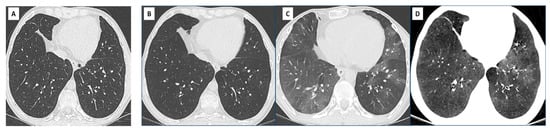

6. Overlap BOS/RAS: Mixed-Phenotype CLAD